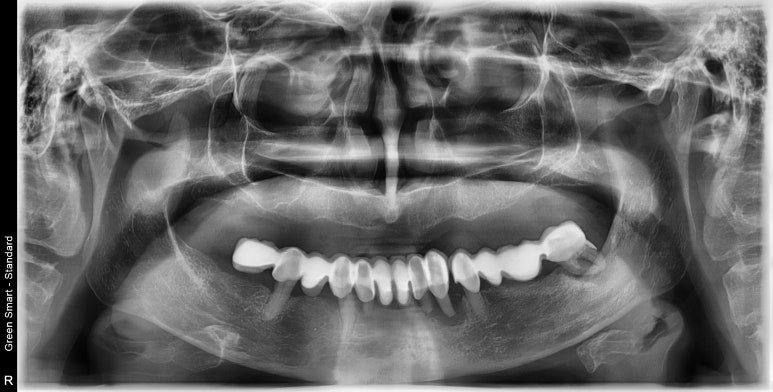

오늘은 머나먼 호주에서 저희 수치과병원을 찾아 #스트라우만 임플란트를 하러 오신 환자분 증례를 나누어 보고자 합니다. 이번 치료 컨셉은 '틀니는 이제 안녕(Say good bye to the dentures)' 이었답니다. 위와 같은 상태로 내원하시게 되었답니다. 상악은 의치, 소위 말해서 틀니 상태로 내원하셨고,...

위와 같은 상태로 내원하시게 되었답니다.

상악은 의치, 소위 말해서 틀니 상태로 내원하셨고, 하악은 브릿지 상태였으나 남아있는 치아의 잇몸 상태가 좋지 않아 발치를 계획하게 되었답니다.

초진 사진

총 7개 치아가 남아있었는데 그마저도 3개 정도를 제외하고는 상태가 썩 좋지 않으셨답니다.